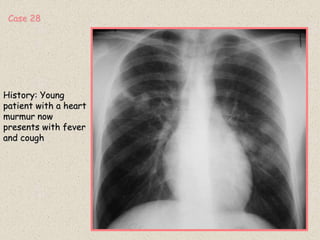

History: Young

patient with a heart

murmur now

presents with fever

and cough

Case 28

RADIOGRAPHIC FINDINGS:

1: Multiple ill defined soft tissue nodules

2: Normal heart

DIFFERENTIAL DIAGNOSIS:

1: Septic pulmonary nodules

2: Pulmonary metastasis

3: Infectious nodules (TB, Fungus)

4. Autoimmune diseases (Wegener’s)

5: Sarcoidosis

Septic Pulmonary Emboli